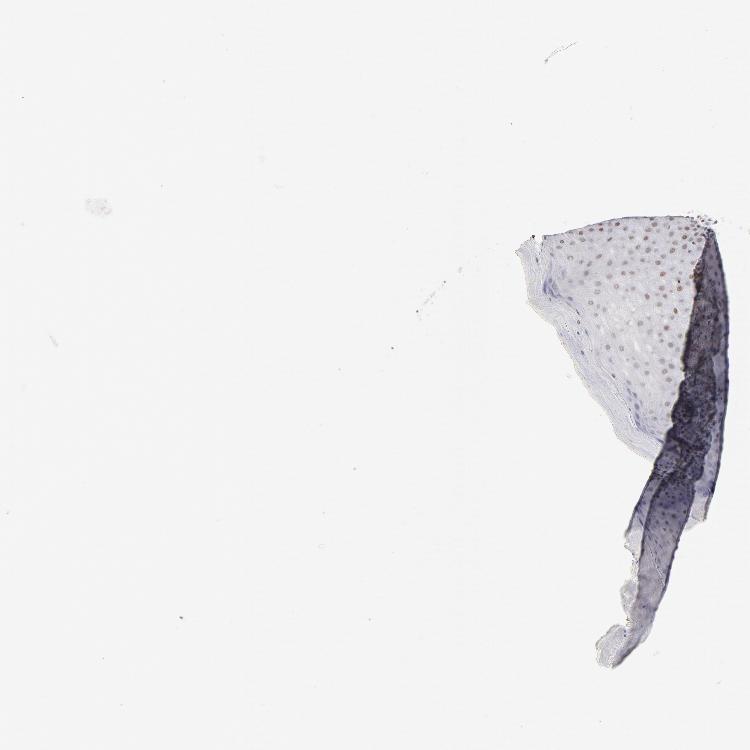

TISSUE PRIMARY DATA CERVIX Show tissue menu

Cervix

CERVIX - Antibody stainingi

Antibody staining in the annotated cell types in the current human tissue is reported as not detected, low, medium, or high, based on conventional immunohistochemistry profiling in selected tissues. This score is based on the combination of the staining intensity and fraction of stained cells.

Each image is clickable and will lead to virtual microscopy that enables deeper exploration of all samples and also displays staining intensity scores, fraction scores and subcellular localization as well as patient and tissue information for each sample.

Antibody HPA003505Antibody HPA003881Antibody CAB018768

Glandular cells HighMediumHigh

Squamous epithelial cells LowMedium-